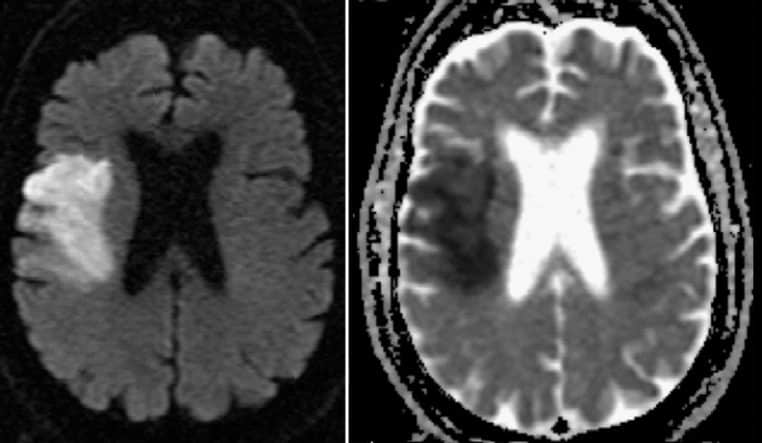

Ce que l’IRM révèle, parfois bien après

Les AVC silencieux laissent des traces typiques visibles en IRM (séquences FLAIR, DWI/ADC ou T2*) : zones d’hyperintensité ou de nécrose témoignant d’un infarctus ancien, parfois multiple. Plus ces traces s’accumulent, plus le risque de troubles cognitifs et de démence vasculaire augmente à long terme. Cela explique pourquoi la prévention vasculaire a un impact direct sur la santé du cerveau.